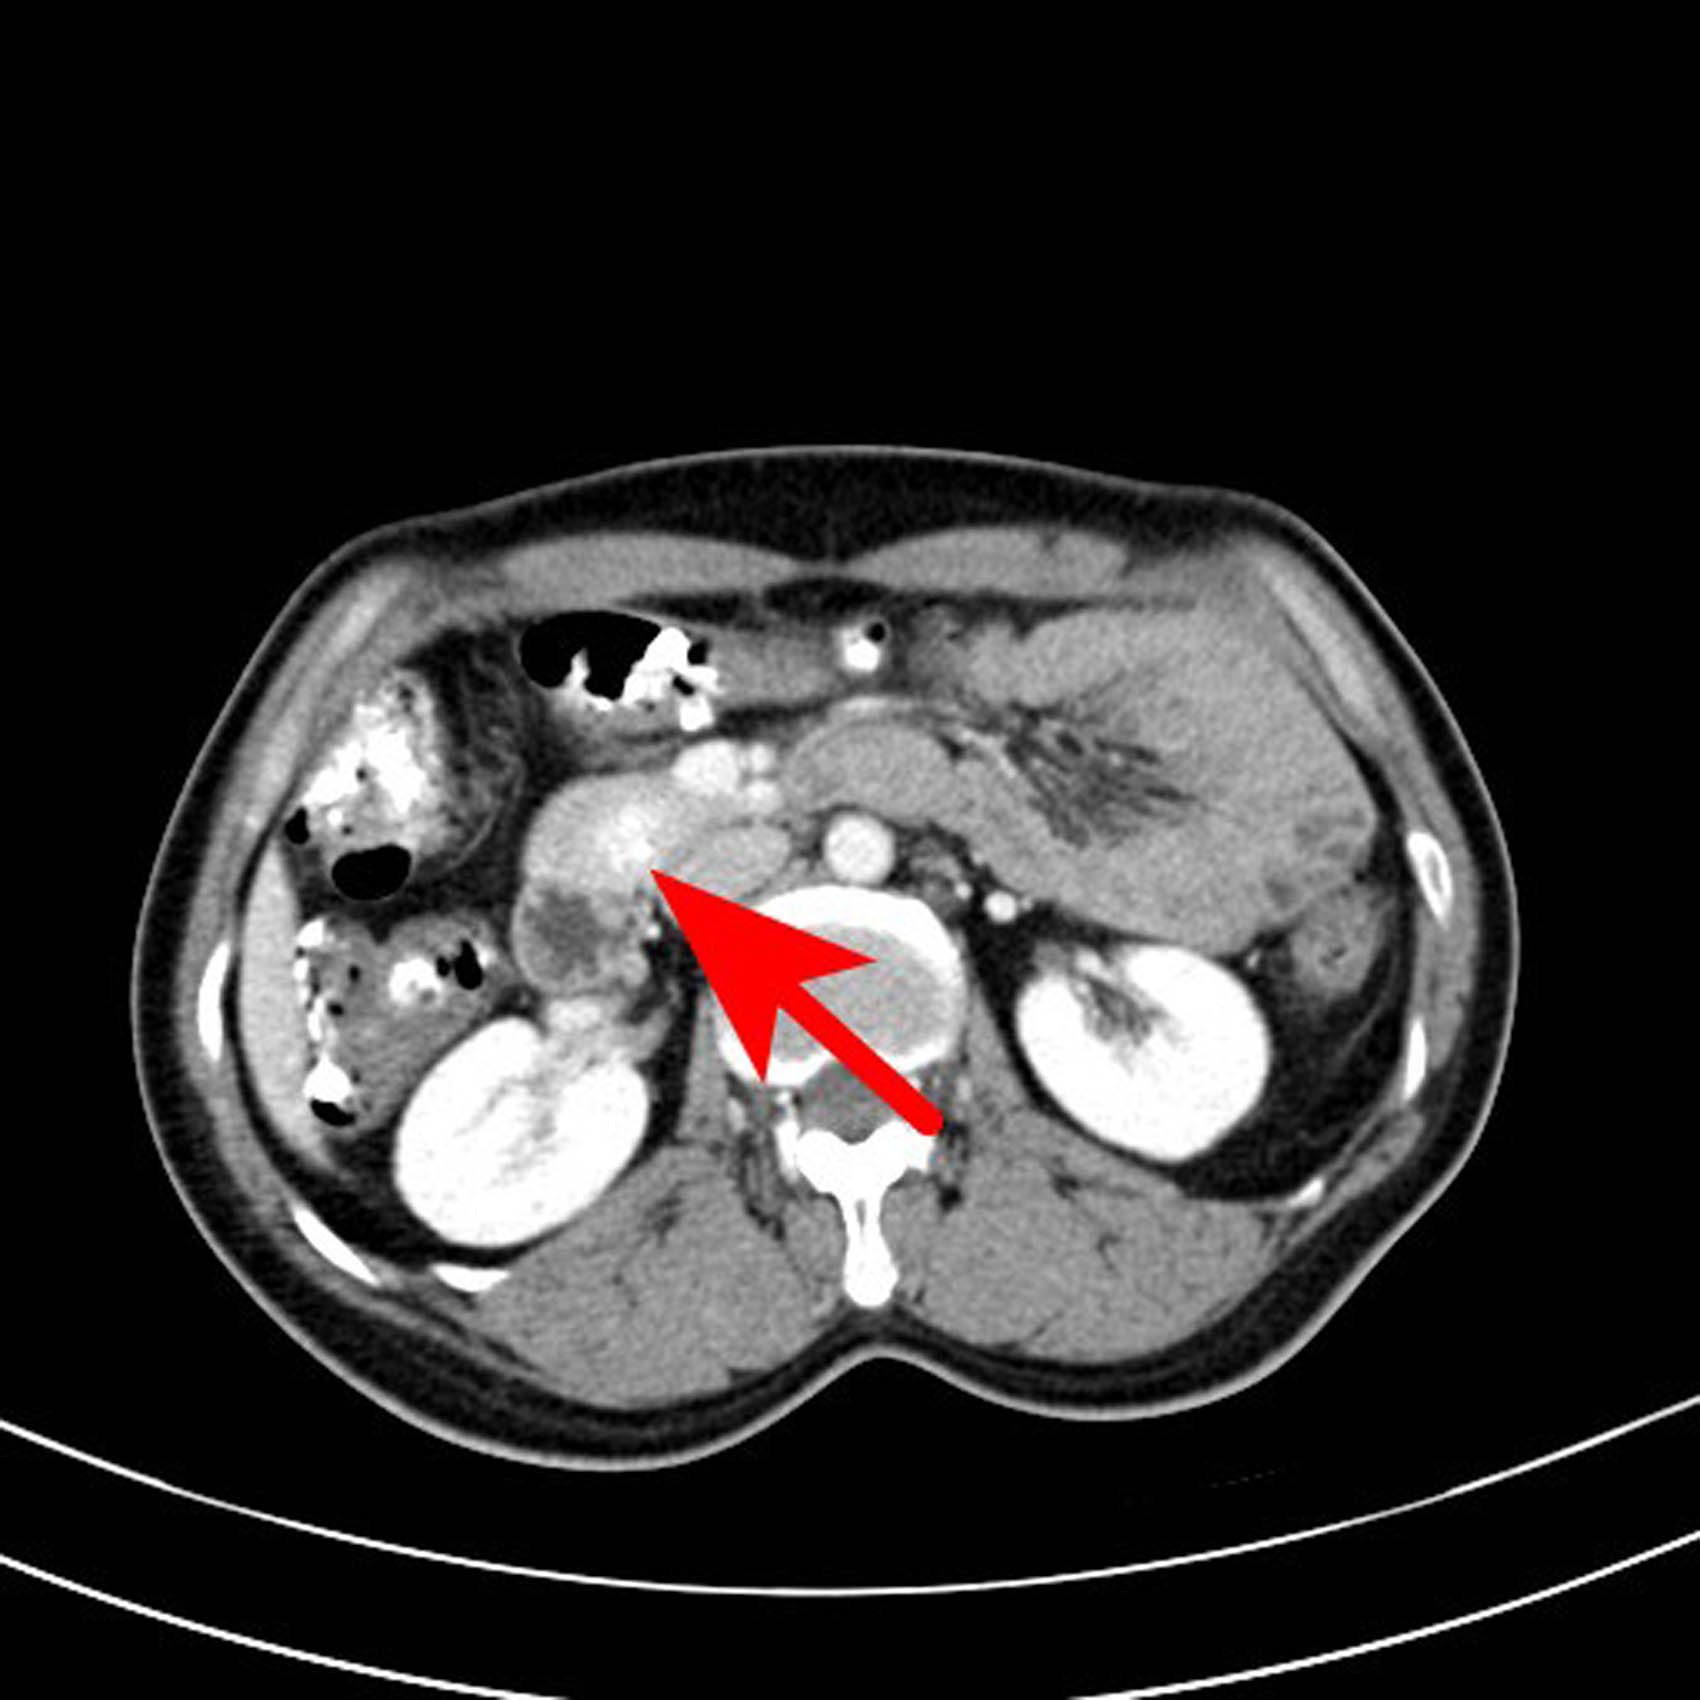

The following imaging tests were conducted. Specifically, the enhanced computed tomography (CT) of the entire abdomen revealed a slightly dense nodular shadow in the head of the pancreas with a maximum transverse diameter of approximately 19 mm, clear borders, and a small cystic hypodense shadow and punctate calcification shadow within, as well as an obviously unevenly enhanced lesion and no enhancement of the hypointense shadow. The CT value was approximately 58 HU on the conventional scan, 192 HU during the arterial phase, and 174 HU during the portal venous phase, and the hypodense shadow was not enhanced. A neuroendocrine tumor was considered (Figures 1–6).

Transverse axial scan of the portal venous phase. The lesion was still high-density with CT value of 174 HU.